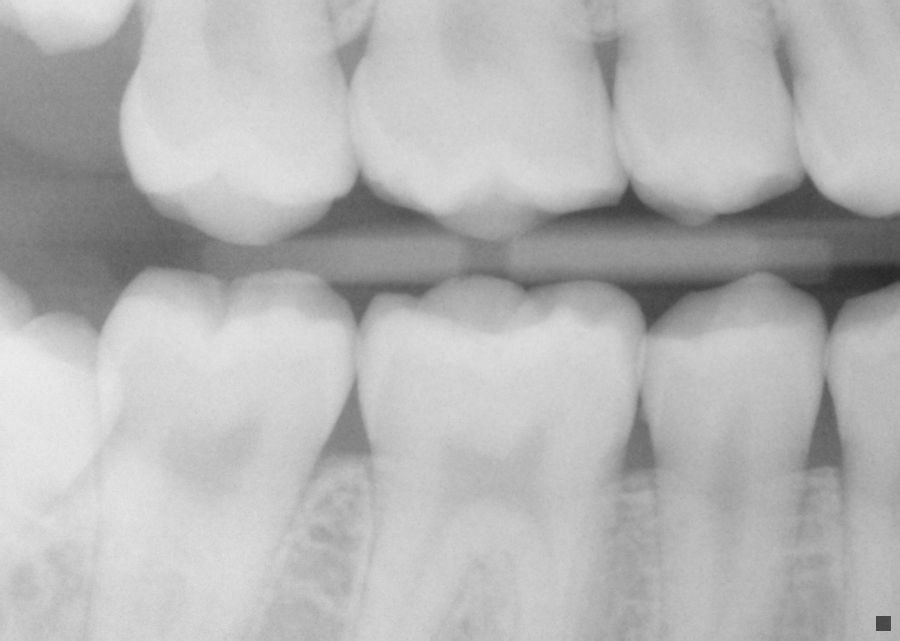

Wisdom tooth abscess Image

Wisdom tooth abscess Image Periodontal Abscess X-Ray pa and epl are normally associated. a periodontal abscess may lead to the destruction of periodontal ligament and alveolar bone whereas a gingival abscess and a pericoronal abscess probably will not give rise to radiographically detectable bone loss. a periodontal abscess forms when pus collects in the connective tissue wall of a pocket. a periodontal abscess. Periodontal Abscess X-Ray.